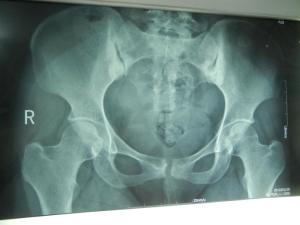

髂骨致密性骨炎是髂骨与骶骨之间耳状关节部分的骨质密度增高。可为单侧或双侧。症状可于半年至数年后自行消失或缓解,此时髂骨的致密性改变并不随之消失。[1]